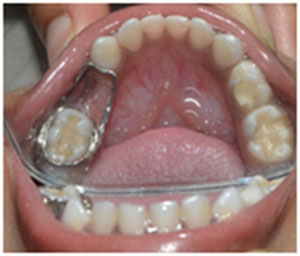

Space maintainers are intra oral appliances (spacers) which prevent teeth from tipping and moving into an extraction area. Space maintainers work by keeping the space open so that adult replacement teeth will be able to erupt into the mouth in the correct location.

Children often need space maintainers after they have had a primary (baby) tooth extracted. A space maintainer can be either cemented to one or more remaining teeth or it can be removable appliance. The space maintainer will need to stay in place until the succedaneous tooth erupts into the extraction area. Space maintainer need to be checked by a dentist twice a year and adjusted if necessary. After the extraction of primary posterior tooth, the adjacent teeth will often move into the extraction space. This unwanted movement of adjacent teeth leads to a loss of space- space that will needed in the future by the succedaneous (adult) teeth.

If extraction space is allowed to close up, the future adult tooth will not able to erupt into mouth correctly. If teeth are allowed to tip into an extraction area, the unerupted future adult tooth may end up being impacted (stuck). Space loss often leads to an adult dentition that is crowded and a child with this problem will need orthodontic treatment later on to correct it.

Space maintainer can also be used as preventive orthodontic appliance. In cases involving moderate crowding in the mixed dentition (6-12 yrs), a LLA (Lower Lingual Arch) space maintainer may be used to prevent unwanted shifting of permanent lower molars.